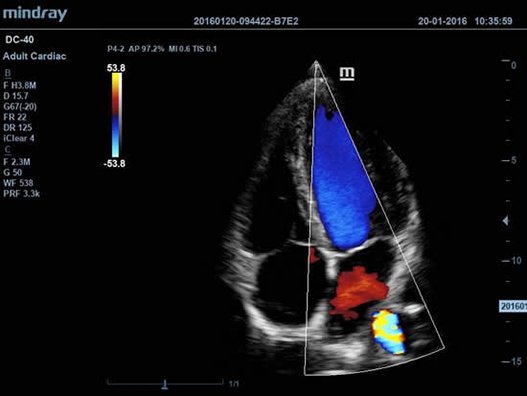

DC-40 имеет особое применение в кардиологической практике, благодаря функции Free Xros CM. Она позволяет отслеживать движения сердечной мышцы в различных фазах и одновременно определять синхронизацию миокарда. Это существенно повышает точность диагноза.

• Функции анатомического режима Free Xros M и Free Xros CM позволяют точно расчитывать анатомические параметры и отслеживать движения сердечной мышцы.

• TDI (Tissue Doppler imaging, including TDI Color, Power, PW and M mode) – пакет тканевой допплерографии, включая цветное картирование, импульсный тканевой допплер, энергетический тканевой допплер и тканевой М-режим;

• Free Xros M™ - анатомический М-режим - это возможность вращения курсора в М-режиме под произвольным углом (при фиксированном положении датчика) и, соответственно, получения графика движения структур сердца в различных произвольных плоскостях;

• Free Xros CM™ - огибающий анатомический М-режим;